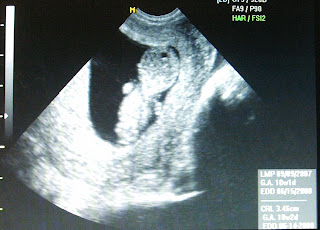

10 week sneak Peak

Well, here s/he is!! I had my first ultrasound on Nov 19, which said I was at 10 weeks 2days. So now, that puts me at about 11 weeks. The dr said everything looked fine and all of my labs came back healthy, so, so far so good. My official due date has been set on June 15, which sounds FOREVER away!! My tummy is already rounding out and and pants are getting a little snug around the waistband, things are showing a heck of a lot faster this time around!! I remember with Annelise I could still wear my skinny jeans when I started seeing her kick. Now if that wasnt' a weird feeling, seeing those little bumps coming from a flat stomach!! But alas, this time around my stomach was definatetly not as flat to begin with, and things are a-stretching faster LOL. But at least I have been feeling better, the morning sickness is almost gone, so if I could just get my appetite back, I'll be as good as new. Right now the only thing that even sounds a little bit good is chips and salsa, I just love the salty of it and could eat it for every meal, either that or cheese quesodillas with salsa, yum. Well, at least it is not pickles and ice cream!!